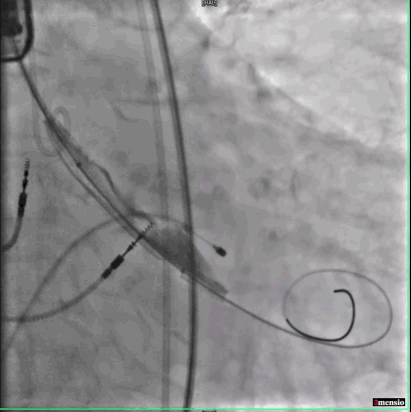

阿婆肾脏功能受损,心衰严重,无法耐受造影剂,做不了传统TAVR手术前评估最重要CT扫描环节。危机时刻,深圳市人民医院心内科心脏彩超室李江华医生,用超声评估的方式代替CT扫描,用超声圆满完成术前评估,体现了深圳市人民医院的超声测量的精确性和可靠性。

跨瓣